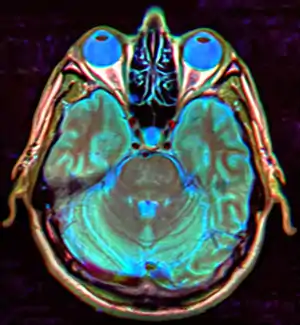

| MRI of Empty Sella | |

Empty sella syndrome is the condition when the pituitary gland shrinks or becomes flattened, filling the sella turcica with cerebrospinal fluid instead of the normal pituitary.[2] It can be discovered as part of the diagnostic workup of pituitary disorders, or as an incidental finding when imaging the brain.[1]